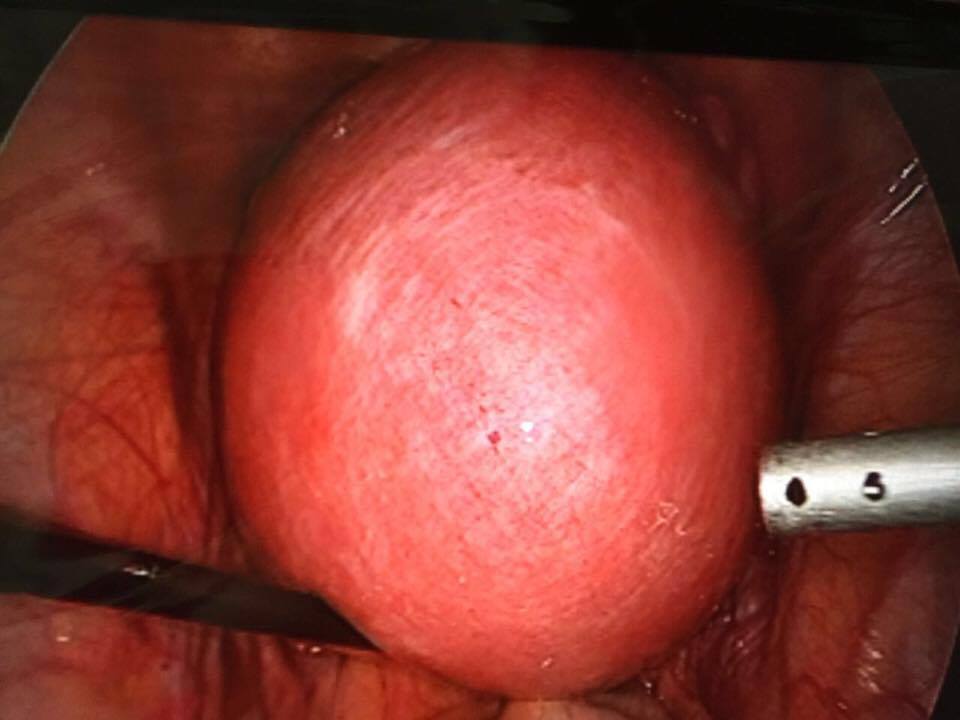

حققت الصحة بمستشفى الولادة والاطفال بمكة نجاحات متتاليه في جراحة المناظير المتقدمة ، حيث تم مؤخرا إجراء العديد من العمليات النوعية وكان أبرزها عمليات إستئصال أورام ليفية بواسطة المنظار وعمليات أورام مبايض ، وقد وصل حجم بعضها إلى مايزيد عن 10 أضعاف حجم الرحم ، وتمت العمليات دون الحاجة لإستئصال الرحم أو المبيض وكانت جميعها من خلال شق صغير لم يتجاوز ( 1 سم ونصف ) و تكللت بالنجاح ولله الحمد ، وقد غادرت غالبية الحالات المستشفى في نفس اليوم أو اليوم التالي .

جديرا بالذكر أن الصحة تقوم بإستخدام هذه التقنية الحديثة في إجراء العمليات النسائية مثل استئصال حمل خارج الرحم ، واستئصال أكياس المبايض، وأورام الرحم الليفية ، واستئصال الرحم ، وعلاج تأخر الحمل وبطانة الرحم الهاجرة .

وقد تم تخصيص غرفة عمليات خاصة لقسم عمليات المناظير النسائية ، بمستشفى ولادة مكة مجهزة بأحدث الأجهزة لإجراء ذلك النوع من العمليات ، كما إن غرفة العمليات تلك مجهزة بأحدث التقنيات التي يتم من خلالها نقل إجراء العمليات عبر البث المباشر إلى أيا من مستشفيات المملكة وكذلك إلى المؤتمرات العلمية مما يتيح الفرصة للنقاش وتبادل الخبرات ، وقد تمكن من خلالها مشاركة ولادة مكة ممثلا بقسم النساء والتوليد من المشاركة في مؤتمر بطانة الرحم الذي أقيم في جده مؤخرا .

يشار الى أن إيجابيات الجراحة بالمنظار متعددة ومنها تكون نسبة حصول المضاعفات الجراحية أقل بعشرات المرات في جراحة المنظار عن الجراحة التقليدية ، إضافة إلى قصر مدة الإقامة في المستشفى ، فالمريضة التي تم إجراء العملية لها من خلال المنظار تخرج في نفس اليوم، أو في صباح اليوم التالي للعملية ، كما أنها قد لا تحتاج إلى مسكنات للألم مثلما هو الحال في الجراحة التقليدية ، ومن الناحية الجمالية ، فإن جراحة المنظار لا تترك أثراً للجروح أو تشوهات على البطن”.